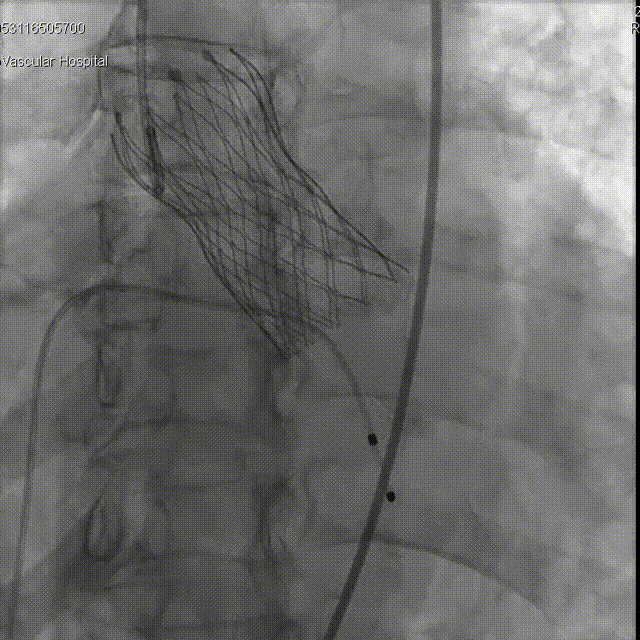

“慢-快-慢”步骤释放瓣膜,20mm球囊后扩 瓣膜形态进一步优化

术后评估

球囊后扩后瓣膜形态良好

术前导管测量压差120mmHg;术后导管测量压差8mmHg